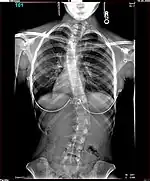

Paul Randall Harrington (September 27, 1911 – November 29, 1980) was an American orthopaedic surgeon. He is best known as the designer of the Harrington Rod, the first device for the straightening and immobilization of the spine inside the body. It entered common use in the early 1960s and remained the gold standard for scoliosis surgery until the late 1990s.[1] During this period over one million people benefited from Harrington's procedure.

Polio patients would sometimes develop scoliosis, a condition where the spine becomes curved laterally (from side to side).[5] Harrington realised that existing treatments for scoliosis, which relied heavily on physical therapy, were inappropriate for patients paralysed by polio, and began to research new treatments. An early method he tried for scoliotic polio patients was manual correction of the scoliotic deformity at the time of surgery, and internal fixation of each facet. There were some benefits to this treatment but Harrington found that the fixation would not hold.[4] The hooks and threaded rods used would corrode and break, causing curvature to return to the spine. Two patients of this procedure died.[5]

The Harrington Rod, or Harrington implant, is a device for the straightening of the spine inside the body, designed by Paul Harrington. The device consists of a stainless steel rod, attached to the spine at the top and bottom of the curve with hooks. Attached ratchets are then tightened to distract or straighten the spine. Following surgery to insert the rod, the patient wears a postoperative plaster cast or brace for a few months, until vertebral fusion has occurred, after which the cast or brace is removed.[5]

The major drawback of the Harrington Rod is that it straightens out the normal front to back curvature of the segment of the spine that is fused, which in many patients results in a flat back deformity, also known as "flatback syndrome". Advances in surgical techniques and technology in the late 1990s were eventually able, in most cases, to correct scoliosis without causing flatback syndrome, leading to the gradual phasing out of the Harrington Rod.[6]